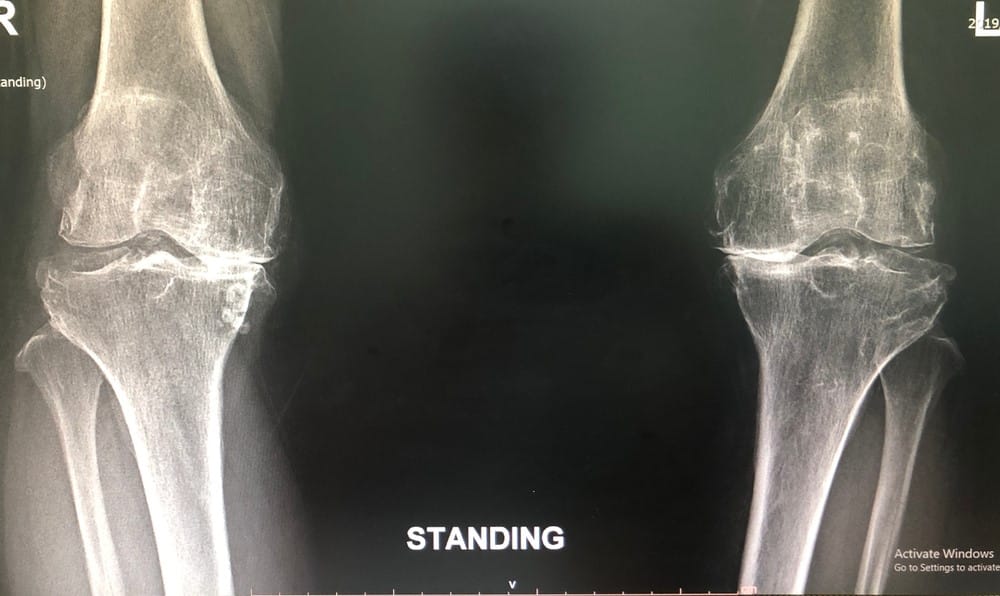

Knee OA is diagnosed via clinical examinations and confirmed by X-rays.

knee osteoarthritis xray diagnosis

Diagnostic tests: